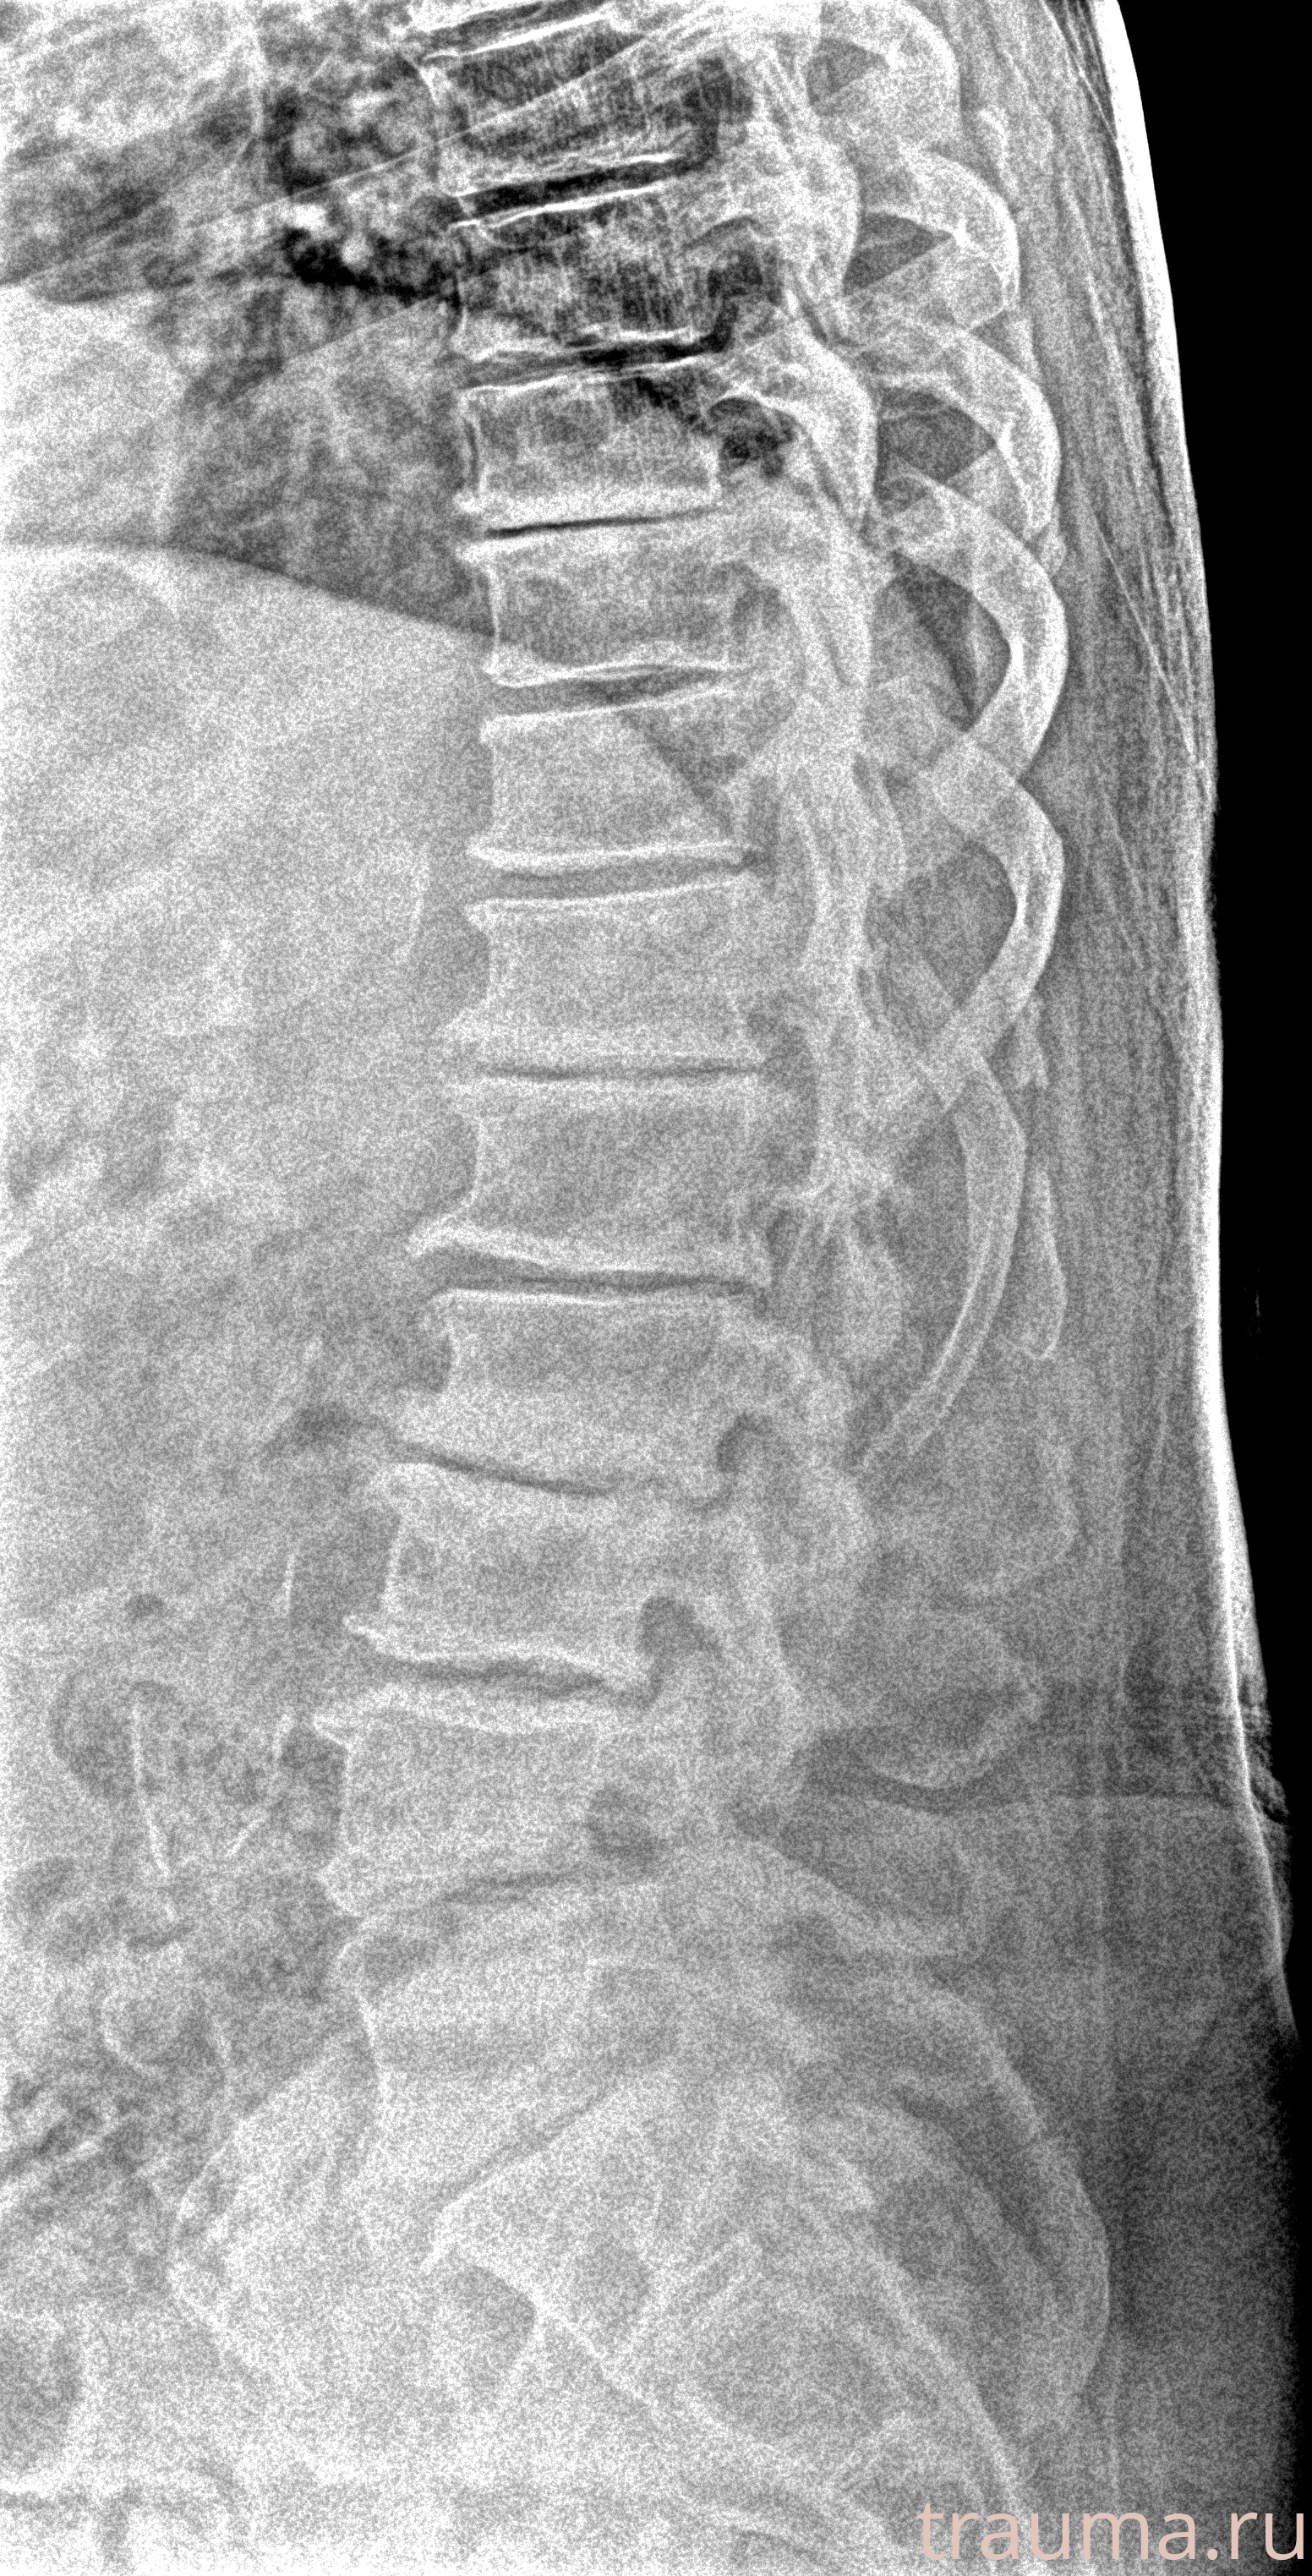

Рентгенограммы

Рентген на дому: по вашему адресу приезжает врач-рентгенолог, травматолог-ортопед с мобильным рентгеновским аппаратом, проводит диагностику травмы или заболевания, делает необходимые рентгенограммы, дает рекомендации по дальнейшему лечению. Получить качественные снимки в домашних условиях возможно благодаря уникальной методике, разработанной МосРентген Центром для института  Склифосовского